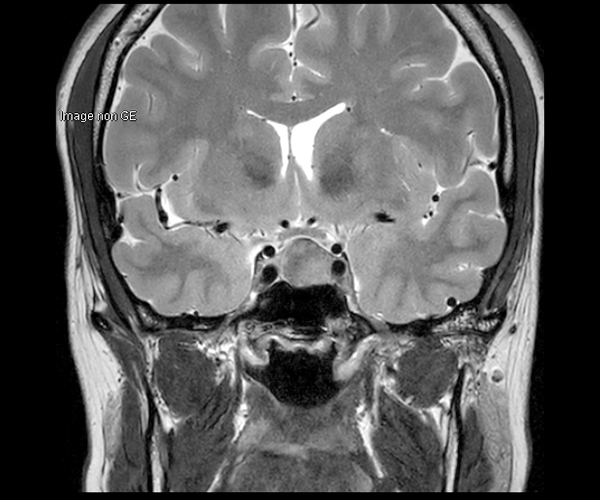

Concernant l’imagerie cérébrale, l’IRM 3T permet d’augmenter la sensibilité de détection de lésions ischémiques aiguës de petite taille, notamment chez les patients adressés pour accident ischémique transitoire (accident vasculaire cérébral), grâce à la séquence de diffusion dont le signal et la résolution sont augmentés.

L’amélioration de la résolution spatiale s’applique à l’exploration morphologique des hippocampes dans le diagnostic de la maladie d’Alzheimer, à la détection de petites lésions de sclérose en plaques ou de métastases, à l’étude fine du cortex dans les épilepsies.

L’augmentation de l’effet de susceptibilité magnétique à plus haut champ permet d’améliorer la détection des hémorragies et est utilisé également dans l’imagerie de perfusion (tumeurs) et l’IRM fonctionnelle (BOLD). L’allongement du T1 à plus haut champ entraîne une meilleure saturation des tissus statiques et par conséquent une augmentation du contraste sang/tissus dans l’AngioIRM.